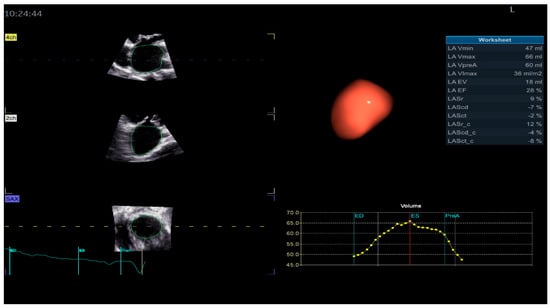

Figure 3.

Left atrium parameters provided by Four-Dimensional Auto Left Atrial Quantification (4D Auto LAQ) software, including left atrium reservoir strain.

The definition of the LA cycle was R-R gating, in which the LA cycle is defined from the peak of the R-wave to the same point of the next cycle. The method presented the LA strain as a monophasic curve (Figure 3). The advantage of the R-R gating method is its availability even during AF [20]. The reference point was set at the left ventricle ED. During the reservoir phase, the LA wall lengthened, and the strain had a positive value. In the other 2 phases, the LA wall shortened, and the strains had negative values. LA longitudinal strain parameters obtained using this technique included LA reservoir strain (LASr), LA conduit strain (LAScd), and LA contraction strain (LASct), and LA circumferential strain parameters included the LA reservoir circumferential strain (LASr-c), LA conduit circumferential strain (LAScd-c), and LA contraction circumferential strain (LASct-c). The studies showed that the total function of the LA was best reflected by reservoir strain [21,22]. From all the 4D LA parameters presented by the software, this parameter was used for the LA function evaluation.

The strain curve provides information about LA physiology (Figure 10). LA activity consists of the following three phases in normal conditions: the reservoir, conduit, and contraction phases [74]. The LA reservoir period follows LV diastole. The LA stretches and fills with blood from the pulmonary veins. During this phase, the strain-positive curve increases, reaching the peak at the LV end-systole, before the MV opening (Figure 10, a). The LASr corresponds to LV isovolumic contraction and isovolumic relaxation. After the MV opens, the LA empties quickly until its pressure equals that of the LV. This phase represents the conduit period. During this phase, the strain decreases (Figure 10, b). After the conduit phase, the LA contracts, expelling blood into the LV, and the strain further decreases; [74] this phase represents the LA contraction period (Figure 10, c) [75,76].

Figure 10.

Left atrium strain curve: a—LA reservoir period; b—LA diastasis phase empties; c—LA contraction.

Four-dimensional echocardiography for LA evaluation offers prognostic and clinical benefits over traditional 2DE analysis [77], overcoming the limitations of 2D analysis by avoiding geometric assumptions about the complex LA shape [78]. Four-dimensional Auto LAQ software analyzes the structure and function of the LA [74], allowing for longitudinal and circumferential LAS quantification during the cardiac cycle (Figure 3) [79]. In the study by Yafasov, M., the median and limits of normality for LA reservoir strain (LASr) were 30.8% (18.4–44.2%) [80]. In this research, the authors used a Vivid E9 (GE Healthcare, Horten, Norway) for image acquisition and an EchoPAC version 204 for post-processing.